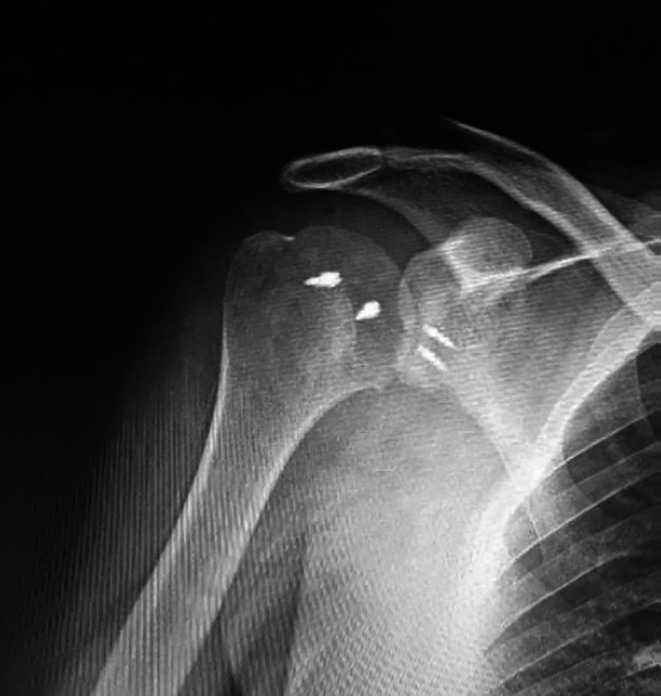

Introduction: Posterior shoulder dislocation with a reverse Hill-Sachs lesion is a rare and complex injury, requiring specialized treatment due to the difficulty in diagnosis, reduction, and addressing both sides of the pathology to reduce the potential for recurrent dislocation.

Methods: A prospective study was conducted at university hospitals, managing 15 patients with neglected locked posterior shoulder dislocation for less than 12 weeks and concomitant engaging reverse Hill-Sachs lesions of less than 40% of the humeral articular surface. They were treated with closed reduction and arthroscopic McLaughlin procedure with posterior labral repair. Patients' assessments included shoulder range of motion, pain levels using the visual analog scale (VAS) score, and functional outcome using the Oxford instability score and the University of California Los Angeles Shoulder Scale (UCLA) with at least 2 years of postoperative follow-up.

Results: All 15 patients reported no recurrent dislocation and restored shoulder motion at the final follow-up. External rotation significantly improved from 0° to a mean of 65° in adduction, at 90° of abduction, the respective measurement was 85° (p < 0.01). Active forward flexion increased from 35° to 145° (p < 0.01). UCLA and Oxford instability scores Showed marked improvement (p < 0.01).

Conclusion: Closed reduction and arthroscopic McLaughlin procedure with posterior labral repair is a safe and effective way for managing patients with locked neglected posterior shoulder dislocations that have been neglected for less than 12 weeks with engaging reverse Hill-Sachs lesion defect, less than 40% of the humeral head.